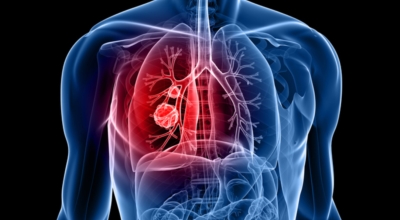

폐암 초기증상 - 흉통

폐암의 초기증상 중에는 흉통이 있답니다. 위치에 따라 요통으로도 진행이 되기도 하는데요 흉통이 발생하는 경우는 폐의 가장자리에 폐암이 발생할 때 나타나게됩니다. 흉막에 암이 인접해 위치하게 되면 바늘로 콕콕 찌르는 듯한 흉통을 느끼게 되며 폐암이 갈비뼈나 다른 부위로도 전이될 경우에도 흉통이 발생하고 요통으로도 발전 할 수 있답니다.

폐암 초기증상 - 호흡 곤란

폐암 환자의 1/4에서 나타나는 일반적인 증상으로 호흡곤란이 일어나는 이유는 다발성 폐전이가 폐 양쪽에서 발견되는 경우 생기게 될 수 있으며 폐암과 또한 악성 흉수가 동반되는 경우 발생해요. 일반적인 때와 다르게 숨이 차는 느낌이 들면서 숨을 들이쉬고 내쉴때 쌕쌕 거리는 소리나 나온다면 폐암 초기증상을 의심해 볼 수 있어요.